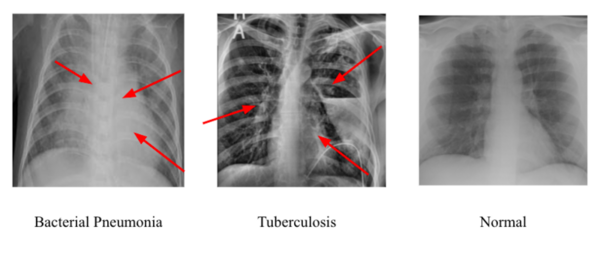

To best identify tuberculosis and pneumonia diagnoses in chest x-rays, the authors compare different deep learning convolution neural networks.